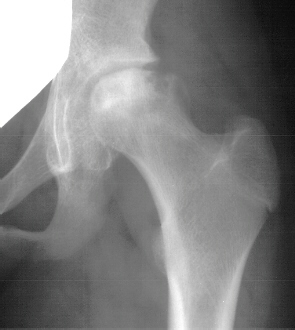

An

important aspect during hip surgery on adolescents is to have

blood available and plan a transfusion.